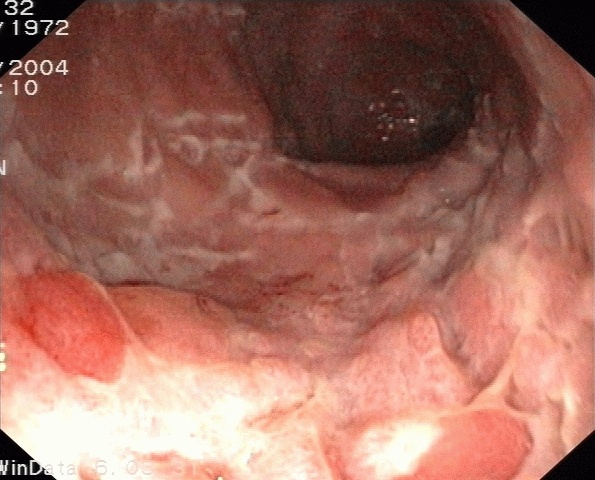

Chronisch-entzündliche Darmerkrankung (CED)

DefinitionChronisch-entzündlichen Darmerkrankungen

Unter chronisch-entzündlichen Darmerkrankungen (CED) werden vor allem zwei Krankheitsbilder zusammengefasst:

- Morbus Crohn

- Colitis ulcerosa

Beide Erkrankungen verlaufen chronisch-schubweise und gehen mit einer inadäquaten Immunreaktion im Darm einher.

Iliitis-Endoskopie.jpg von Joachim Guntau.J. Guntau at de.wikipedia, CC BY-SA 2.0 DE, via Wikimedia Commons

InfoMorbus Crohn

Es handelt sich um eine chronisch-entzündliche Darmerkrankung, die alle Abschnitte des Gastrointestinaltrakts befällt und schubweise verläuft. Die Ursache ist multifaktoriell. Eine gefürchtete Komplikation ist insbesondere die Fistelbildung.